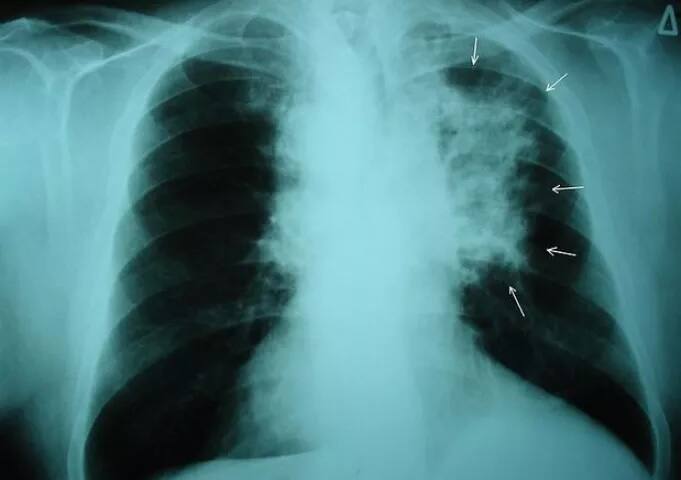

ਪ੍ਰਦੂਸ਼ਣ ਨਾਲ ਫੇਫੜਿਆਂ ਦੇ ਕੈਂਸਰ ਦਾ ਖ਼ਤਰਾ, ਇੰਝ ਕਰੋ ਬਚਾਅ

ਆਮਤੌਰ ’ਤੇ ਇਹ ਮੰਨਿਆ ਜਾਂਦਾ ਹੈ ਕਿ ਫੇਫੜਿਆਂ ਦੇ ਕੈਂਸਰ ਦੀ ਮੁੱਖ ਵਜ੍ਹਾ ਸਿਗਰਟਨੋਸ਼ੀ ਹੈ ਪਰ ਠੋਸ ਸਬੂਤ ਮਿਲੇ ਹਨ ਕਿ ਫੇਫੜਿਆਂ ਦੇ ਕੈਂਸਰ ਦੇ ਵਧਦੇ ਮਾਮਲਿਆਂ ਵਿੱਚ ਪ੍ਰਦੂਸ਼ਿਤ ਹਵਾ ਦੀ ਭੂਮਿਕਾ ਵੀ ਵਧ ਰਹੀ ਹੈ। ਇਸ ਖ਼ਤਰਨਾਕ ਬਿਮਾਰੀ ਤੋਂ ਬਚਾਅ ਲਈ ਤੁਸੀਂ ਜ਼ਿਆਦਾ ਪ੍ਰਦੂਸ਼ਣ ਵਾਲੀ ਥਾਂ 'ਤੇ ਮਾਸਕ ਪਹਿਨ ਕੇ ਜਾਓ।